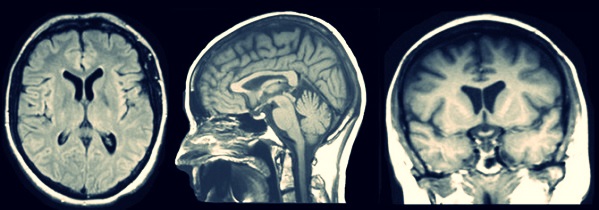

У большинства людей томография ассоциируется со сканированием головного мозга. Действительно, показания к обследованию МРТ в этой области достаточно обширны:

- травмы и повреждения черепа;

- подозрение наличия опухолей;

- определение масштабов инсульта;

- диагностика заболеваний сосудов головного мозга.